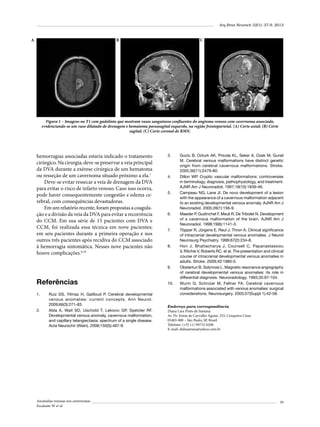

“ponto hipocampal” (Figura 1 A-B).

Figura 1 (A-B) – Imagens de RM ilustrando os cortes utilizados no plano axial e coronal para localizar o “ponto".

temporal basal) (Figura 2).

Figura 2 – Corte coronal na topografia da cabeça do hipocampo,

ilustrando a mensuração do corredor cirúrgico. (A): ponto lateral

basal; (B): ponto medial superior; (C): ponto medial inferior;

D: ponto basal.

A distância média (a) canal auditivo-ponto hipocampal foi de 31,9 mm [mínimo (c) 24,7 – máximo (b)

39,6 mm] (Figura 3 A-B).

A distância média ponto lateral basal-ponto medial

superior 1 foi de 40,9 mm (mínimo 36,3 – máximo 45,1

mm) (Figura 2).

inferior 2 foi de 45,8 mm (mínimo 36,8 – máximo 53,4

A distância média do ponto basal 3 foi de 7,4 mm

(mínimo 4,1 – máximo 10,1 mm) (Figura 2).

foram identificados dois formatos: tipo I – 4,0-8,0 mm

(13 pacientes: 59%) e tipo II – 8,1-10,1 mm (9 pacientes:

40%) (Figuras 4 e 5).

Figura 3 – (A) Localização do “ponto hipocampal” na superfície

cutânea e (B) na superfície óssea.

Figura 4 – Convexidade temporal basal tipo 1 (59%).

Neste estudo, identificou-se esse ponto craniométrico (ponto hipocampal), localizado em média a 31,9

mm do canal auditivo externo (Figura 3A e B).

O corredor cirúrgico foi delimitado com três pontos

anatômicos (Figura 2).

O vértice lateral desse triângulo representa o local da

corticectomia. Na base estão as estruturas-alvo (corpo

amigdaloide e hipocampo). Esse planejamento permite

orientar o acesso ao ventrículo através da porção anteroinferior da parede lateral (“área livre”), evitando a

lesão da radiação óptica (Figura 2).

A profundidade da convexidade temporal basal é

variável. Foram identificados dois formatos (tipo I e II)

(Figuras 4 e 5). É relevante considerar essa classificação

no posicionamento cirúrgico da cabeça. No tipo II é

recomendada maior deflexão lateral para obter melhor

ângulo de acesso (Figuras 4 e 5).